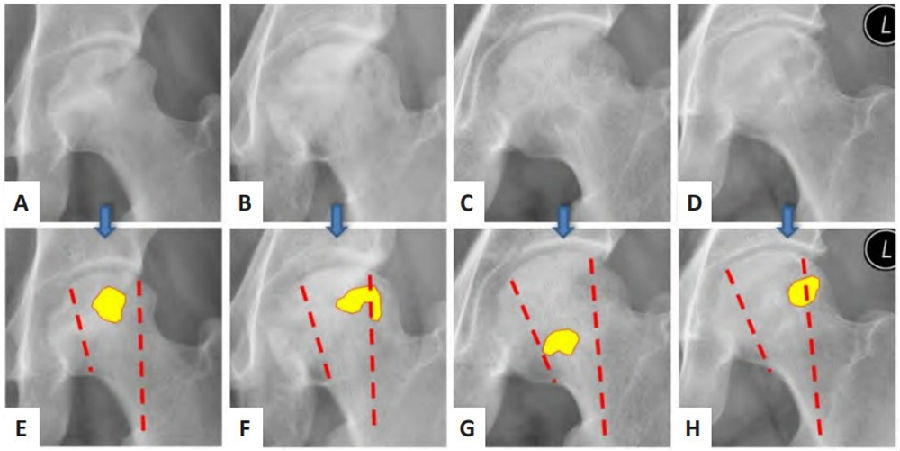

图3. A-D分别为4例激素性股骨头坏死患者左侧股骨正位 X 射线片,E-H通过用黄色高亮标记上述患者在X射线片中囊性变发生的位置

热力图显示囊性变的热点位置一般在股骨头的中外侧柱,与股骨头内压力骨小梁的位置大致重合(引自中国组织工程研究 2023, 27(31):4996-5001)